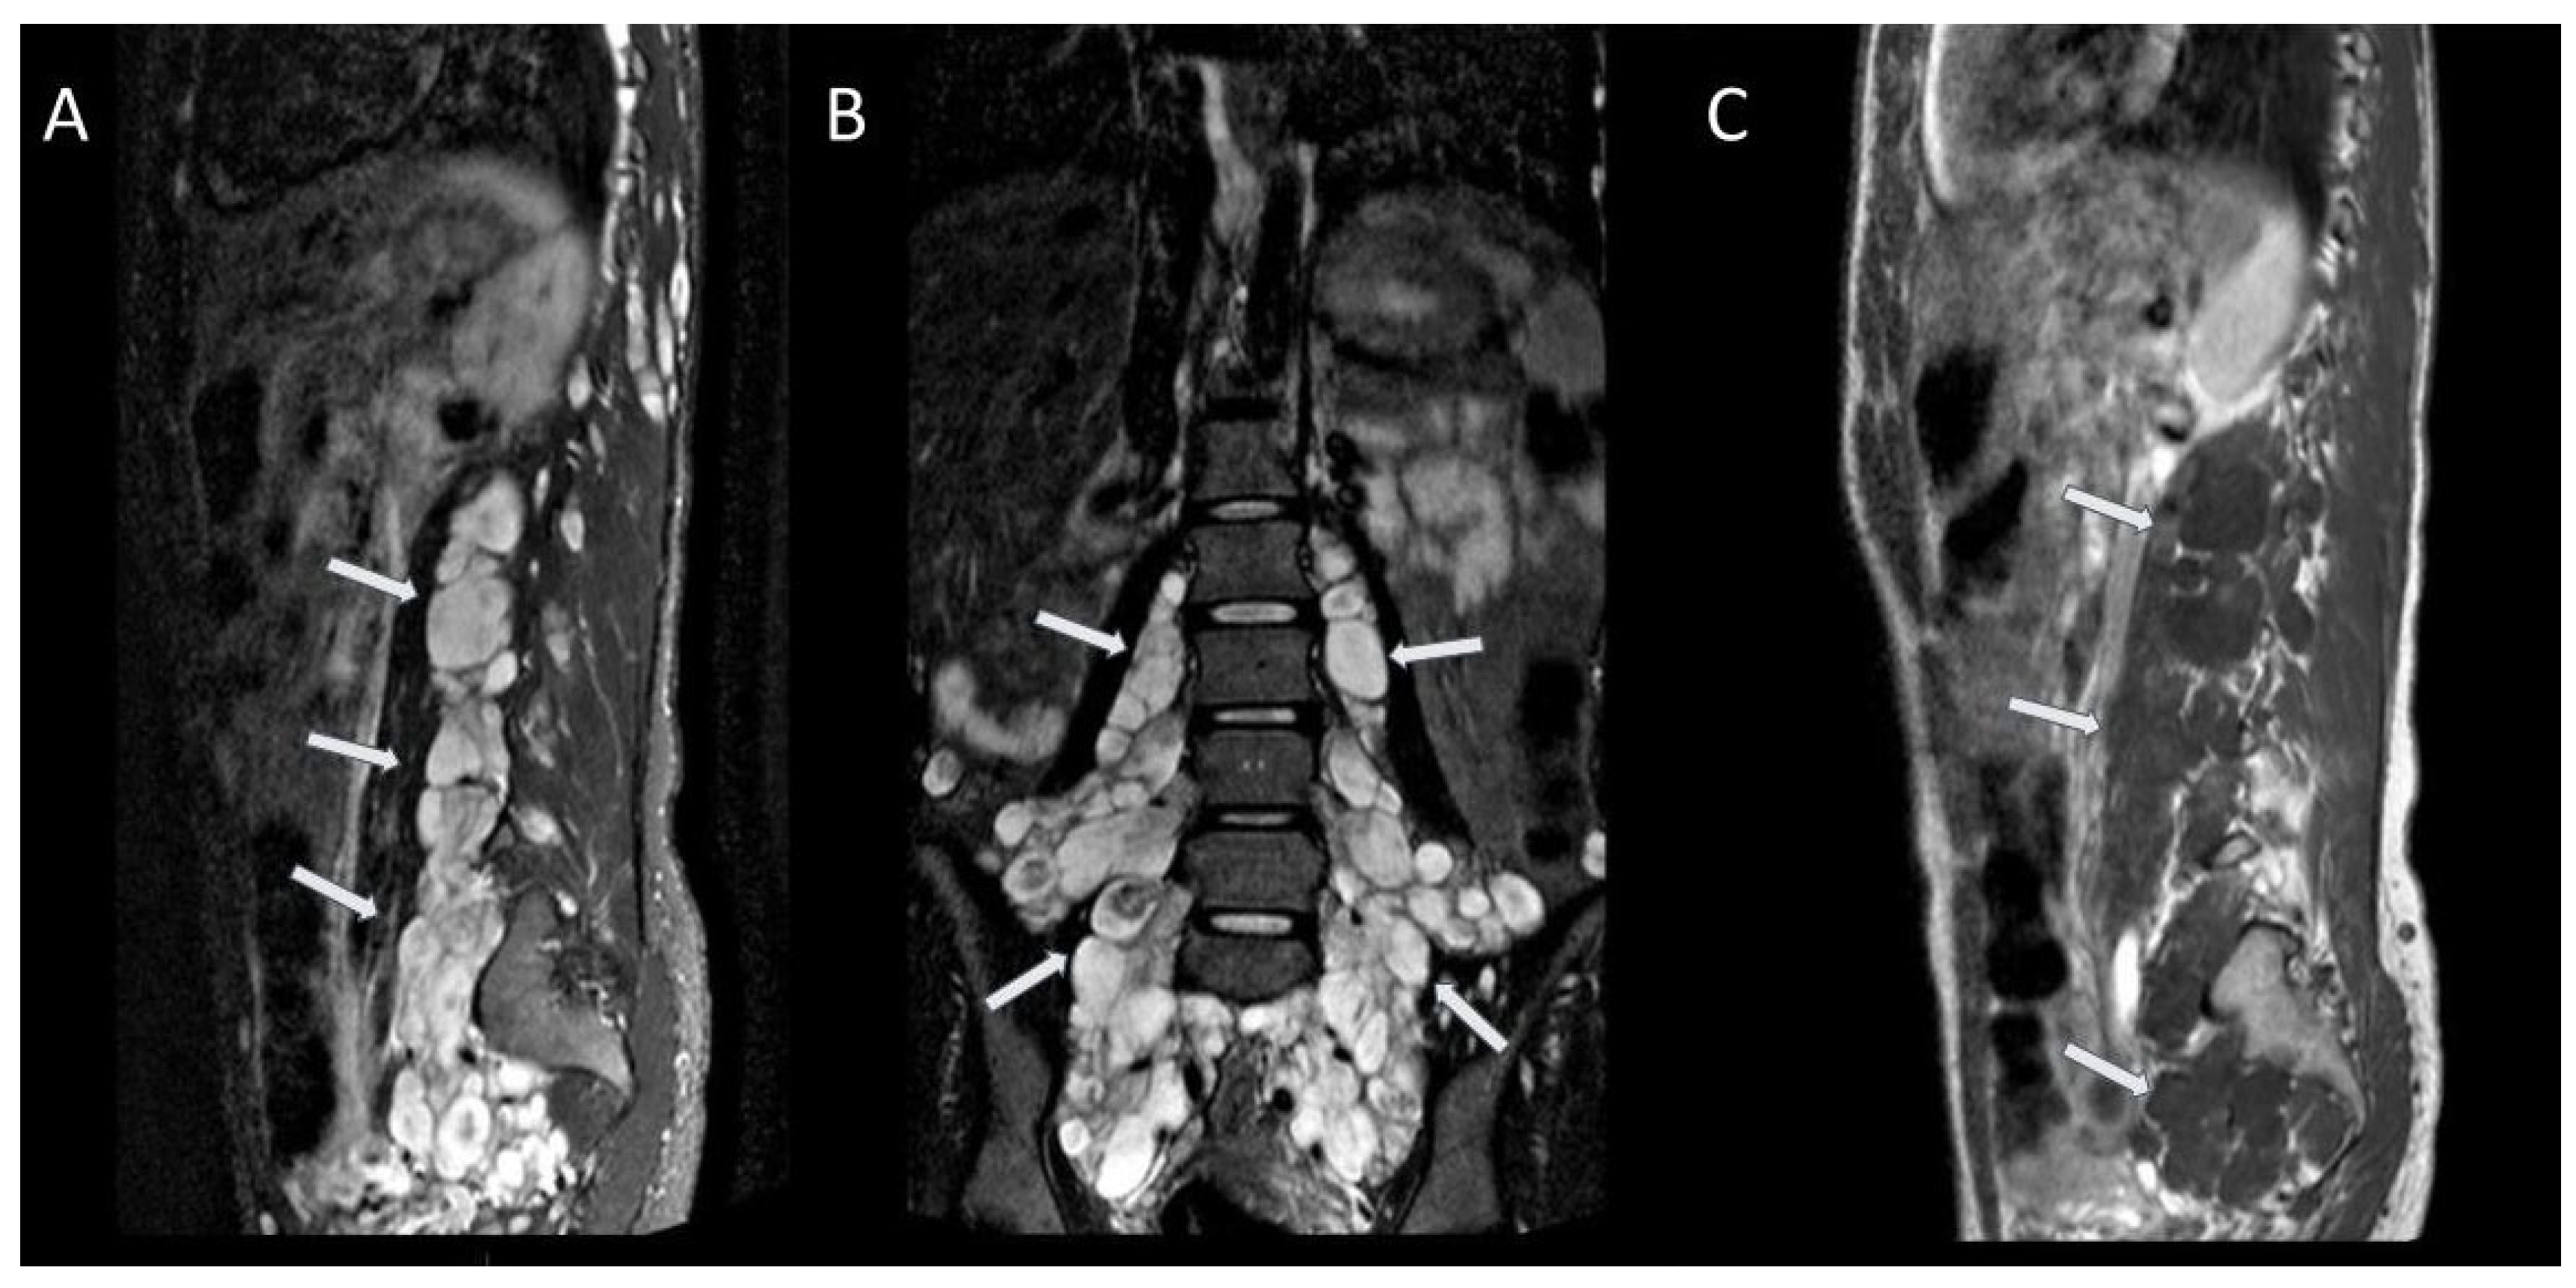

2.4. Spinal Tumours

| Spinal tumours: peripheral nerve sheath tumours and intramedullary tumours | 40–96% | Benign neurofibromas represent the majority of spinal tumours, while intramedullary lesions are rarely observed; |

| Neurofibromas usually show hyperintense signal on T2-weighted images with central hypointense target, and hypointense signal on T1-weighted images, with heterogeneous contrast enhancement. | ||

| Features suggestive of malignant nerve sheath tumour: enlarging tumour, tumour size > 5 cm, ill-defined margins, lack of a central hypointense target on T2-weighted images, heterogeneity with central necrosis. | ||